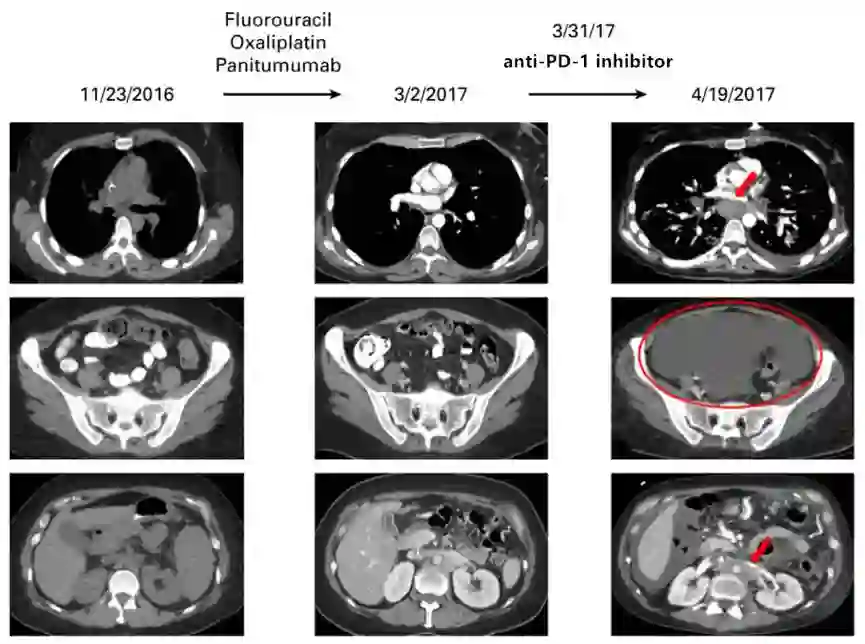

患者女,36岁,患胃食管交界处腺癌[10]。在接受氟尿嘧啶、奥沙利铂和帕尼单抗二线治疗时,病情稳定(下图,左边和中间),由于患者出现亚厘米淋巴结病变,方案改为PD-1抑制剂。治疗3周内,患者纵隔、腹膜后淋巴结进展迅速,出现大量腹水,进展速度较检查点阻断前4个月增加6.4倍,肿瘤负荷较免疫治疗前影像学增加460%。随后治疗改为氟尿嘧啶、奥沙利铂和曲妥珠单抗,但患者在使用PD-1抑制剂1.5个月后死亡。原发肿瘤的分子表达谱发生多个突变(Foundation Medicine, Cambridge, MA),包括MDM2、ERBB3、ARAF、CDK4和EGFR的扩增,以及PIK3CA、FRS2、GLI1和IKZF1的突变。TMB较低,微卫星稳定。未进行免疫组化检测PD-1和PD-L1。该病例提示,MDM2扩增可作为免疫检查点抑制剂的潜在进展标志物。